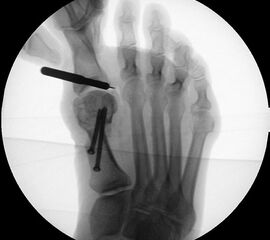

Instrumentarium für die minimalinvasive Vorfußkorrektur.

Abbildung 3